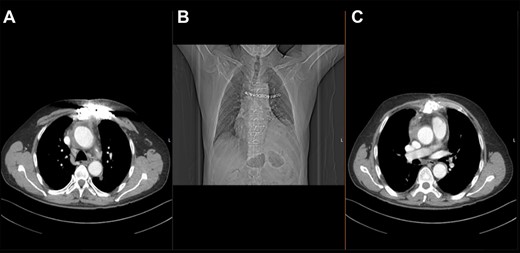

At almost 6 years after the initial surgery, the patient was transferred to our unit with a chronic sternal fistula. The computed tomography (CT) scan showed almost complete destruction of the manubrium sterni on the left side, a fistula path into the anterior mediastinum and an abscess collection around the ascending aorta (Fig. 1). The echocardiography ruled out any significant valve regurgitation or stenosis, endocarditis or aortic root abscess. Pseudomonas aeruginosa was cultivated from the fistula.

Preoperative thoracic CT scan; (A) image indicates the sternal defect caused by osteomyelitis and the infected hematoma surrounding the native aortic arch; (B) topogram indicating the sternal defect caused by osteomyelitis in coronary sectional plane; (C) image indicates the sternal defect caused by osteomyelitis and the infected hematoma surrounding the aortic prosthesis.